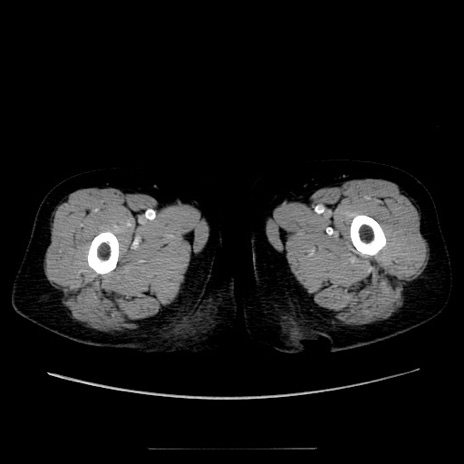

症例5(横断像)

【症例】70歳代女性

【主訴】お腹が張る

【現病歴】1週間くらい前から腹部膨満の自覚あり。昨日夜から増悪したため、本日救急外来受診。

【身体所見】意識清明、BT 36.5℃、BP 165/106mmHg、HR 80bpm、SpO2 98%、腹部:膨満、軟、自発痛・圧痛なし、触診にて不快感あり、腸蠕動音:減弱

【データ】WBC 12600、CRP 1.04